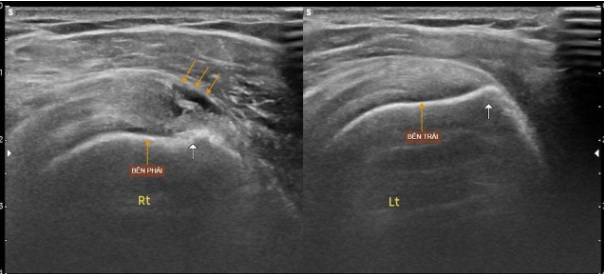

Kết quả siêu âm cho thấy bệnh nhân bị rách bán phần gân cơ trên gai, một trong những gân quan trọng của khớp vai, thường bị tổn thương khi phải thực hiện các động tác đánh bóng lặp lại với cường độ cao.

Hình ảnh siêu âm so sánh gân trên vai hai bên, bên phải các thớ gân bị mất, bên trái bình thường. Ảnh: Văn Thụ